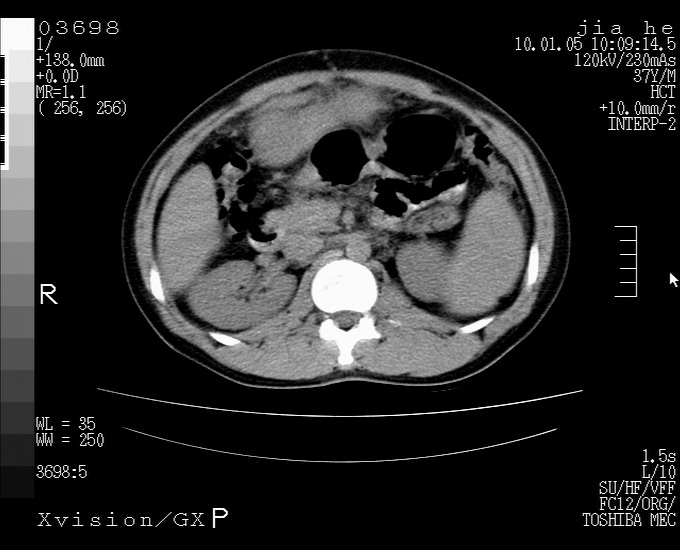

标题: CT23988:男,40岁,B超提示腹部肿物,请各位老师给看看。 [打印本页]

标题: CT23988:男,40岁,B超提示腹部肿物,请各位老师给看看。

2.脾大,肠系膜密度增高,有多发索条影,胰腺边缘毛糙,腹膜增厚,推测有肝硬化,门脉高压,腹膜炎和/或胰腺炎

3.肝左叶巨大站位,并腹腔淋巴结肿大,肝癌或肝间叶来源恶性肿瘤,也不排除大网膜间质瘤侵及肝左叶

肝癌并腹膜后淋巴结转移

外生性肝癌并腹膜后淋巴西结转移!

考虑肝左叶外侧段癌并腹膜后淋巴结转移.建议增强进一步检查.